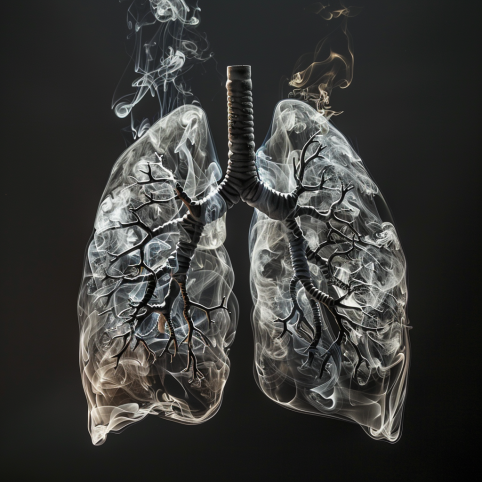

Jaki to konflikt:

Konflikt dużego lęku na terytorium